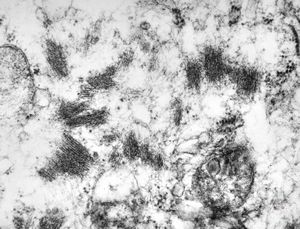

F,56y. | nemaline myopathy v.s.